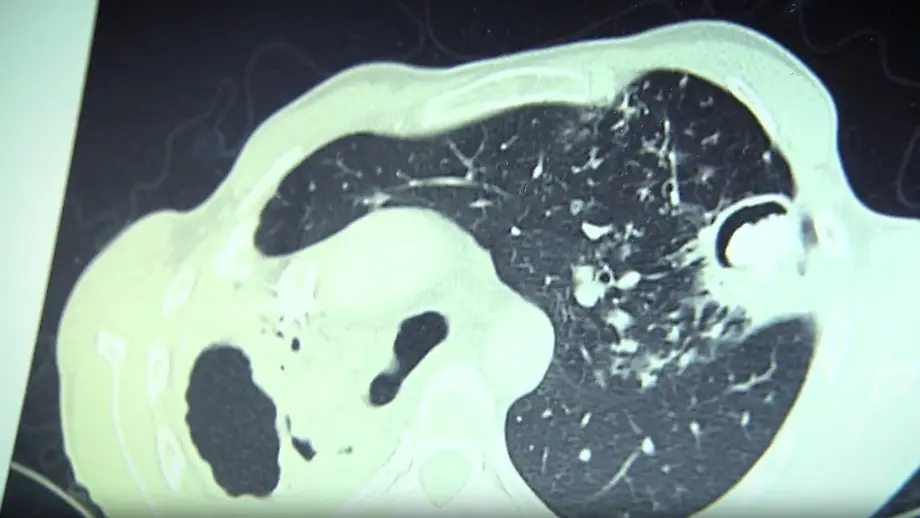

11.05.2025, 08:26 UhrFieber, Husten, Gewichtsverlust: Die ersten Symptome der Tuberkulose ähneln einer Erkältung. Die bakteriellen Erreger aber verursachen die "am häufigsten zum Tod führende Infektionskrankheit", wie Mediziner Thomas Theo Brehm erklärt. Zuletzt nimmt die Verbreitung der Krankheit zu - auch in Deutschland.